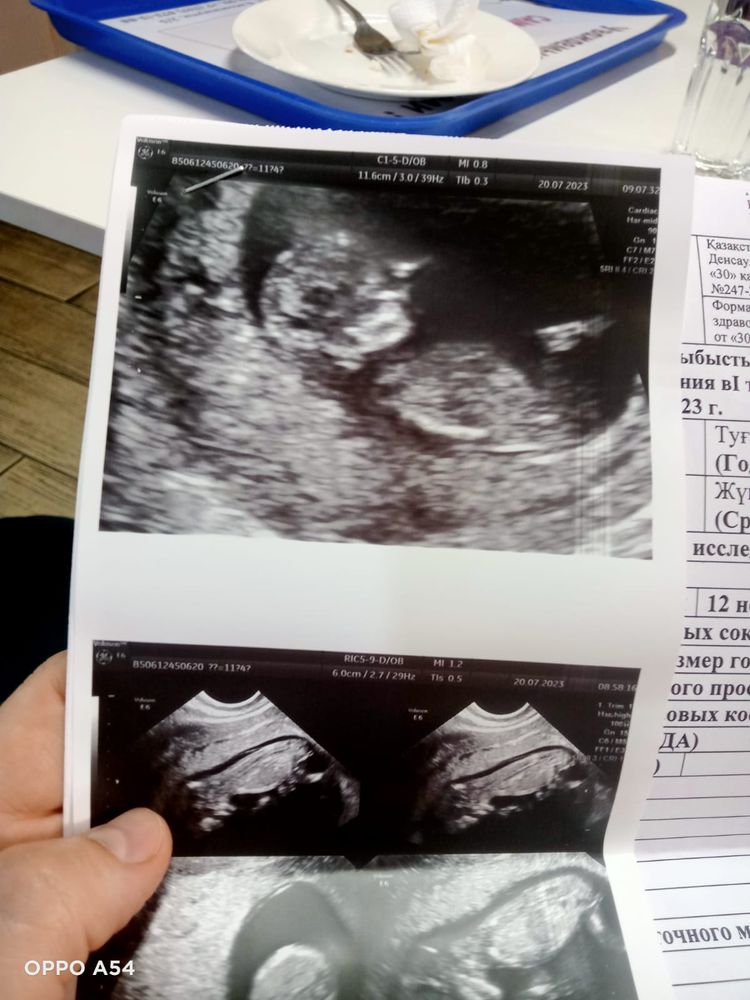

Ну вот и прошла я первый скрининг. По данным УЗИ все хорошо. Развитие на 12 недель ровно , хотя по месикам 11 и 4 дня. Пельмешка очень активный детёныш, все УЗИ передавал приветы с экрана монитора. Сердцебиение как было 159 ударов так и осталось.

Удивило меня, что прям там уже человек человек))) даже пальчики на ручках ножках видно!

Пол точно не сказали, карапуз весь извертелся. Так что ждём второй скрининг!